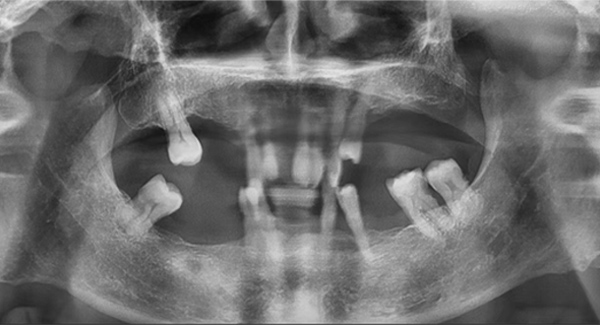

另一個全口種植案例,除了缺牙、骨量等常見問題外,他的咬合還是內傾的深覆合,這是最大的治療難點。也就是說,患者的咬合不正常,如果按常規的思路種植后直接戴臨時牙冠,當他半年后戴上最終牙冠時,整個咬合可能不會理想,到那個階段再去調整咬合,效果可能不太好,人也比較受罪。

我決定做難但正確的事情。種植手術完成后,我讓患者戴上了樹脂義齒重建咬合,讓他通過日常的咀嚼,在原本平整的下牙義齒上慢慢形成新的尖窩對應關系。前后花了半年時間,才達到穩定且可重復的咬合狀態。這時候,再制作第二幅臨時義齒,也就是有解剖牙尖和尖窩交錯關系的臨時牙,讓患者再次適應咬合3個月。最后,我把患者適應并且滿意的咬合關系轉移到他的最終牙冠上,完成了修復治療。

這位患者不到60歲,但由于后牙全部缺失多年,殘留的前牙已松動且上下無法接觸,他基本沒辦法正常咀嚼,人非常消瘦。完成治療后我跟蹤了這個病例一年,從前后對比照片可以看出,能正常吃東西后他的臉上漸漸也有肉了。